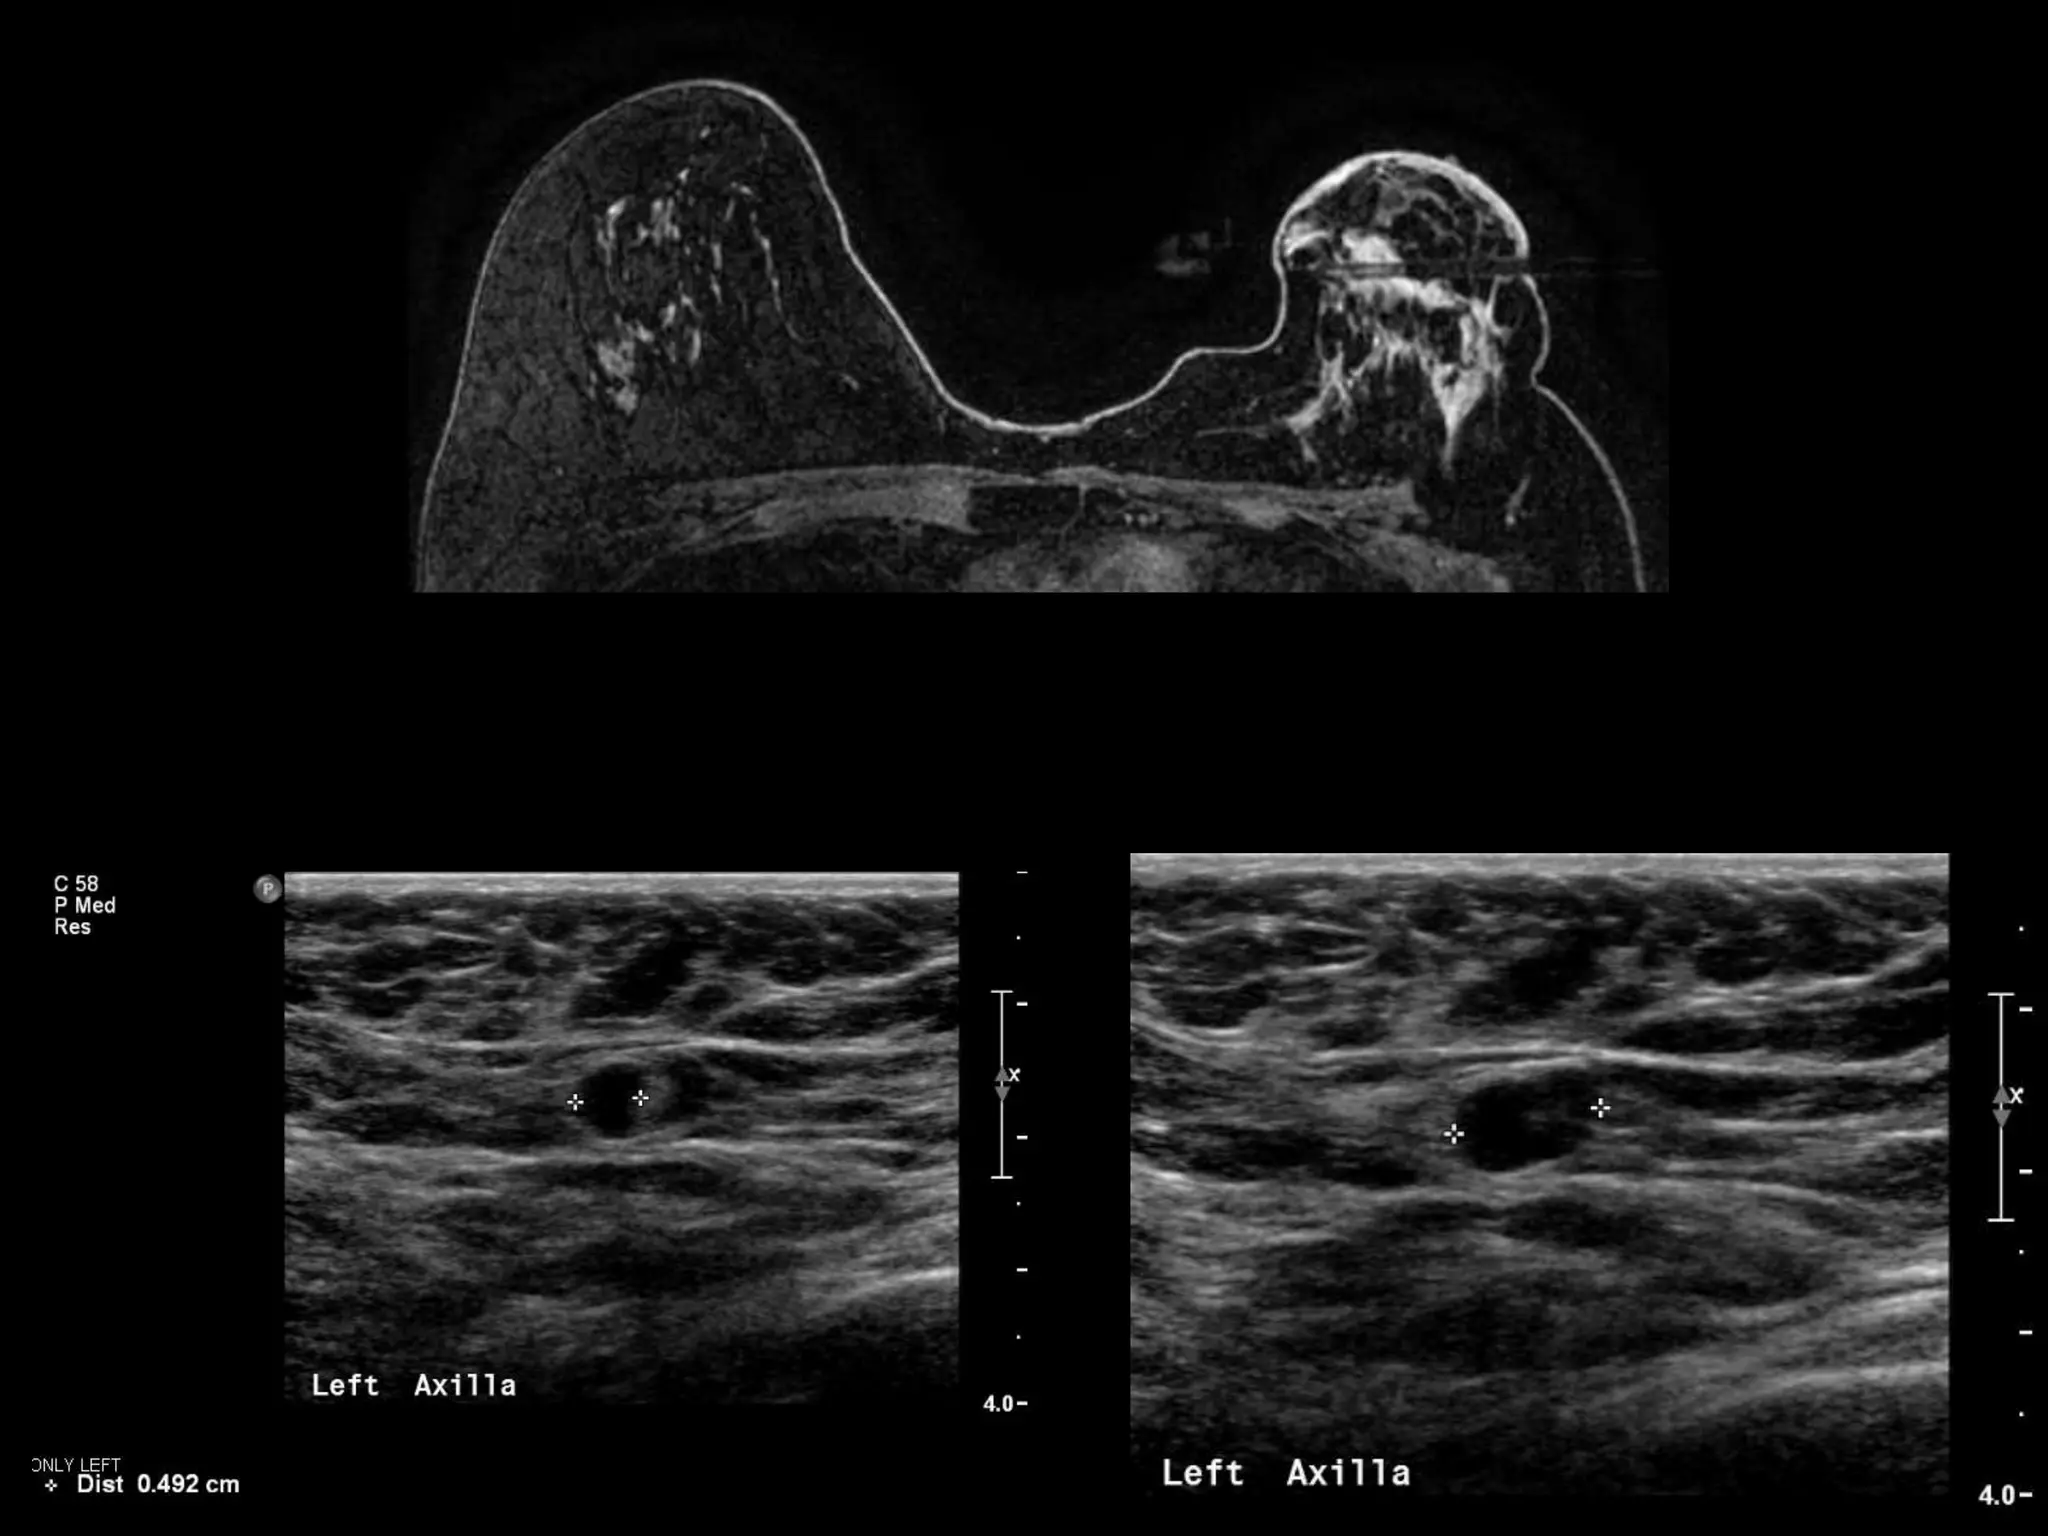

HISTORY

โ€ข 65 yo female

โ€ข Presents from OSH with worsening โ€žleft

breast swellingโ€Ÿ for 8-9 months

โ€ข New 1 month history of โ€žchange in left

nippleโ€Ÿ

Grade 2 Invasive Lobular Carcinoma

with LN positive for Metastatic Adenocarcinoma

SURGERY โ€“ Mastectomy with LN dissection

Invasive Lobular Carcinoma

โ€ข Sensitivity of MRI up to 95%

โ€“ Changes in clinical management up to 50%

โ€“ Changes in surgical management up to 28%

โ€ข Kinetics โ€“ progressive more typical than

washout